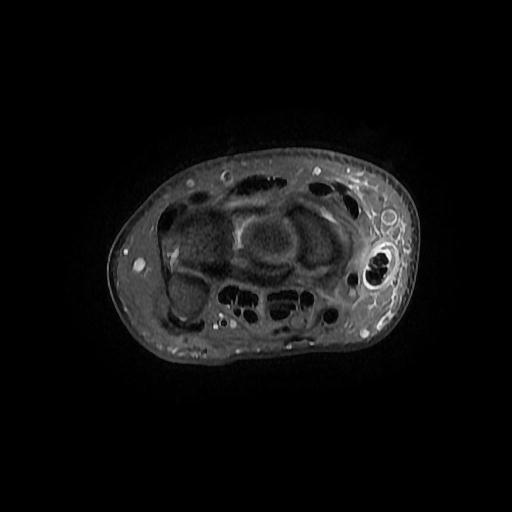

Bitte befunden und beurteilen Sie die vorliegende MRT des Handgelenks. Anamnese: Handgelenksschmerzen radialseitig.